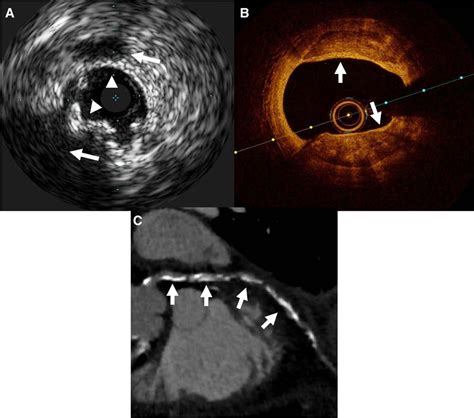

Coronary Artery Calcium scoring is a specialized type of computed tomography (CT) scan that focuses on the heart. Unlike traditional CT scans, CAC scoring specifically looks for calcium deposits in the coronary arteries. These deposits are a sign of atherosclerosis, a condition where plaque builds up in the arteries, narrowing them and increasing the risk of heart attacks and strokes.

During a CAC scan, the patient lies on a table that slides into a CT scanner. The scanner takes multiple X-ray images of the heart from different angles. A computer then processes these images to create a detailed picture of the coronary arteries. The amount of calcium in the arteries is measured and given a score, known as the Agatston score.